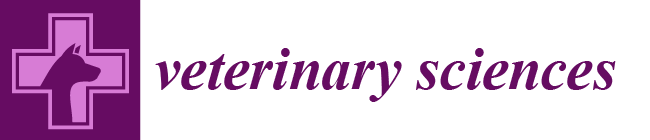

4.2. Thoracic LUS